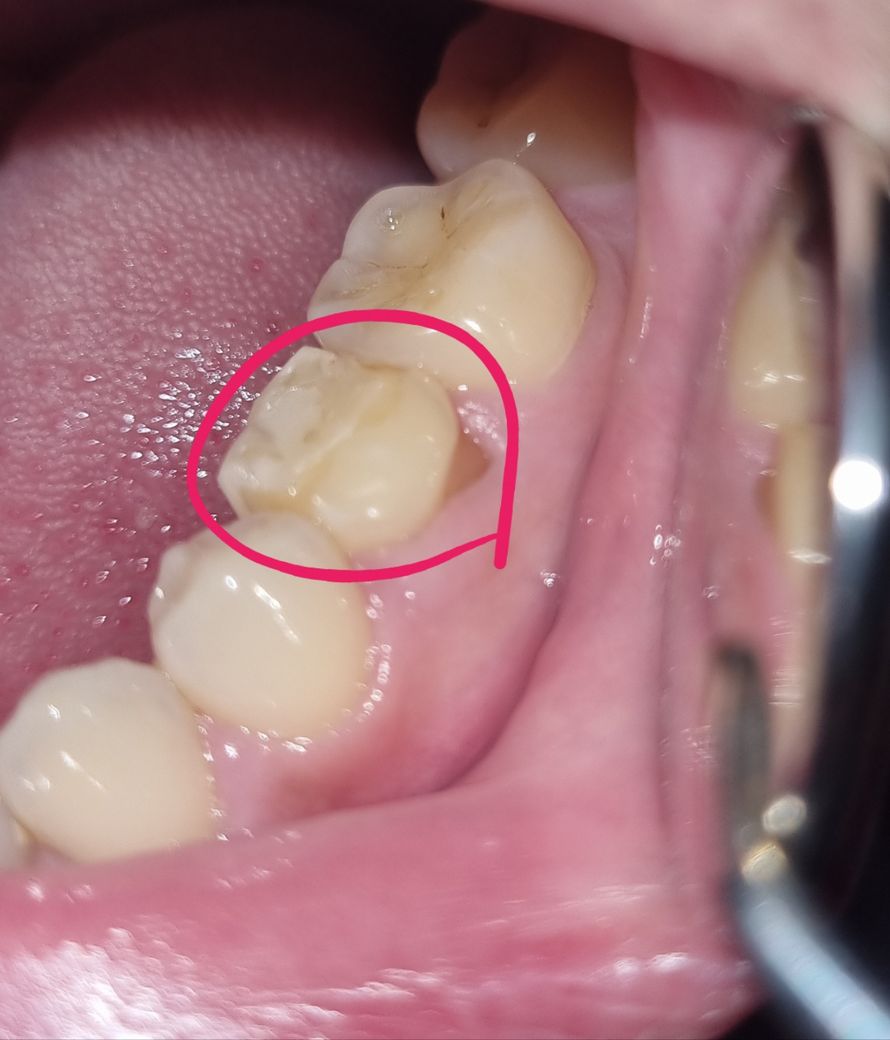

밥먹다가 갑자기 왼쪽 유치가 욱신거려서 거울로 봤더니, 이빨이 세로로 잘려있더라구요??

반대쪽 유치는 잘려있지는 않은데, 왼쪽 유치가 잘린 위치와 모양 그대로 얕은 자국이 있습니다.

• 1번 째 사진

장기간 치아의 사용으로 인해 파절의 가능성이 있기 때문에 시린듯한 통증 등이 심하시다면 제거 후 추가적인 치료를 받으시는 것을 추천드립니다.